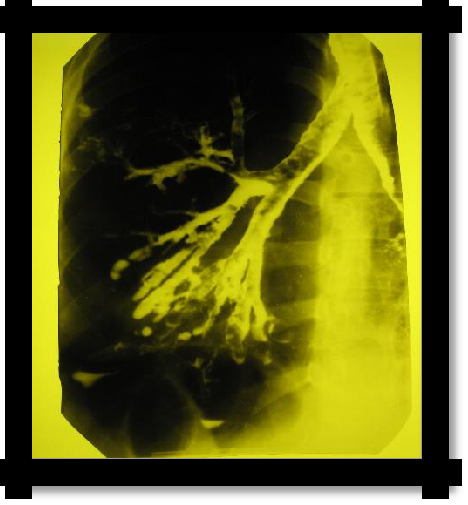

1. X-ray: amplification, ―cellularity‖ of the pulmonary pattern (not always detected). The "gold standard" of the study is bronchography (contrasting of the bronchi with iodolipol), reveals the characteristic saccular and spherical extensions of the bronchi. Recently, computed tomography

(CT) with contrast has been widely used.

Pic 2.8 Bronchography